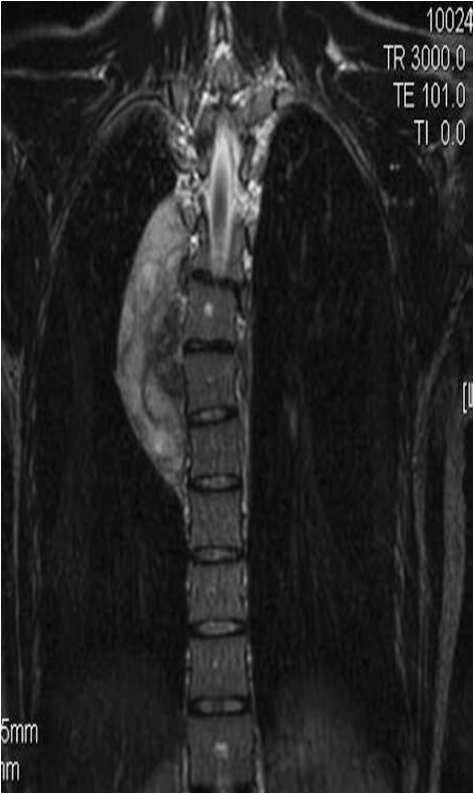

CXR findings are that of a small lung with ipsilateral mediastinal shift, and in one third of cases the anomalous draining vein may be seen as a tubular structure paralleling the right heart border in the shape of a Turkish sword (“scimitar”).

Scimitar syndrome is associated with congenital heart disease, ipsilateral diaphragmatic anomalies and vertebral anomalies